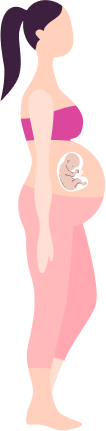

Taking Care of You and Your

Baby Pregnancy Timeline